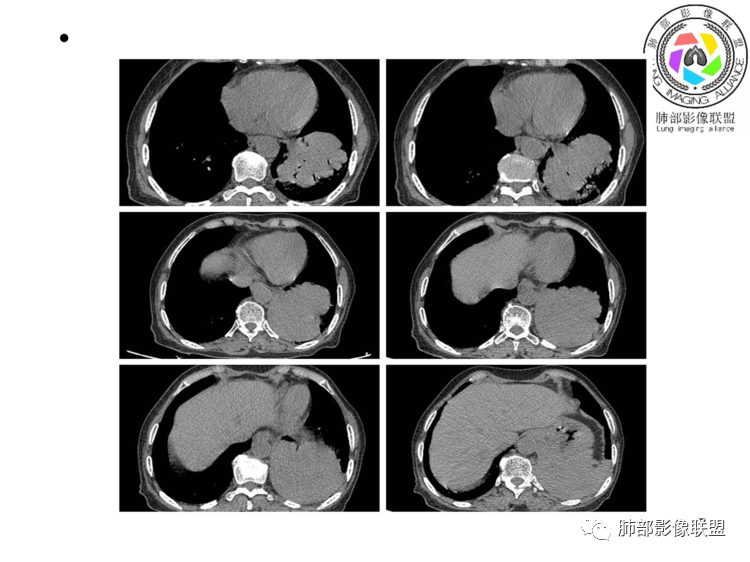

团片,内有支气管扩张,血管飘浮,不均匀强化,累膈肌似侵及脾脏,考虑恶性,淋巴瘤?肉瘤?

左肺下叶团块,边缘膨隆分叶,支气管部分阻塞、部分进入扩张,密度不均,延迟强化,血管走行正常,病灶与左侧膈肌分界不清。考虑恶性肿瘤:1淋巴瘤;2肉瘤样癌。

左肺下叶巨大实性肿块,支气管进入后阻塞,血管走行自然,增强中度均匀强化,无明显坏死。与膈肌分界不清,是否有侵犯导致腹痛症状?

考虑恶性肿瘤,低分化腺癌或者淋巴瘤?

老年女性,上腹部疼痛为主诉,CT所示左肺下叶肿块,左肺下叶支气管变窄,局部阻塞,病灶可见分叶,内见僵硬稍扩张的支气管,增强扫描病灶中度强化,内见血管造影征,首先考虑恶性病变,腺癌和淋巴瘤需要考虑,转移瘤待排除。

老年女性,以上腹痛就诊,左肺下叶团块影,边界清,可见分叶,延迟强化,内未见明显坏死,可见支气管充气扩张,血管走形自然,考虑淋巴瘤

老年女性,上腹痛就诊,CT可见左肺下叶巨大肿块,支气管进入后变窄堵塞,血管走行自然,内可见稍扩张支气管,增强均匀强化,与膈肌分界不清,考虑为恶性,淋巴瘤或腺癌可能

老年女性,左肺下叶软组织肿块,密度较均匀,边缘膨隆分叶,临近支气管截断,肿块内可见支气管穿行,与膈肌分界不清,增强后动脉期轻度均匀强化,静脉期呈渐进性强化,欠均匀,内血管走形如常,可见血管漂浮,整体感觉病灶偏软,考虑淋巴瘤可能大,鉴别腺癌。

患者老年女性,上腹部疼痛一周,无呼吸道症状,查体无阳性体征。血常规、尿常规、肝肾功能正常。肿瘤标志物CA125稍升高。胸部CT:左肺下叶肿块灶,边缘欠光滑,边界欠清楚,见分叶、血管集束征象,内见支气管扩张,增强中度强化,见血管漂浮征象。综合考虑恶性病变,淋巴瘤可能大,鉴别肺癌。

左下肺不规则巨大肿块,下叶支气管部分阻塞,部分扩张,与左侧膈肌分界不清,增强延迟强化,可见血管造影征,考虑恶性,淋巴瘤可能大,鉴别腺癌

老年女性,上腹部疼痛一周,肿标CA125升高。胸部CT:左肺下叶巨大肿块,分叶,密度不均,与左膈肌分界不清,内见枯枝征,部分支气管进入后截断,增强中度延迟强化,见血管漂浮征。胃壁不均匀增厚。考虑:恶性肿瘤病变伴阻塞性炎症,淋巴瘤?腺癌转移?鉴别TB、隔离等。

老年女性,左下肺大肿块、深分叶,考虑恶性肿瘤。纵隔肺门淋巴结无明显肿大,不支持小细胞癌;支气管进入后截断、肿块破坏力不强,不支持鳞癌,内部血管走行自然,不怎么支持腺癌,支持淋巴瘤;肉瘤似乎内部很少见支气管。

左肺下叶实变影,形态尚规则,外缘欠光滑,呈膨胀性生长,叶裂推移,近段支气管穿行,支气管略扩张,平扫密度均匀,增强后可见穿行血管,老年女性,无感染症状,实验室检查肿瘤标志物高,考虑恶性:1:淋巴瘤;2:腺癌;3:IMT

左下肺肿物,有分叶及血管飘浮征,定性恶性,无胸膜牵拉及毛刺,提示收缩力差,可排除腺癌。女性,肿块内坏死不明显(鳞烂心)不首选鳞癌。老年女性,血管飘浮,特别是膈肌受累首选淋巴瘤

定位,肺内,血管支气管穿行

定性,恶性,腺癌跟淋巴瘤鉴别

腺癌支持点就是常见病,发病率高,CEA高。不好解释血管穿行比较自然。病灶整体偏软,所以淋巴瘤放前面